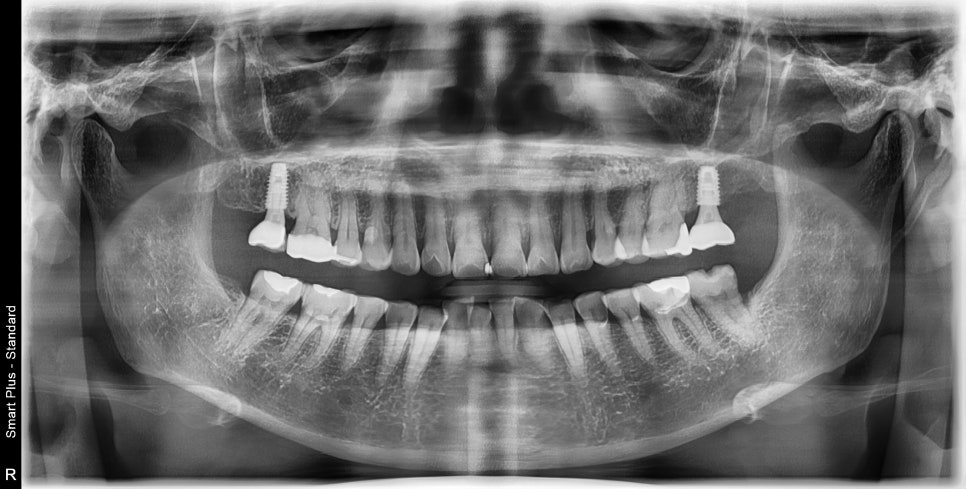

이미 엑스레이에서 근단부 염증이 심하시고, 입천장 쪽에는

고름 주머니까지 형성이 되어있었습니다.

동요도까지 생겨서 재 신경치료는 불가능해 보입니다.

발치 전 CT를 찍어 주변 치조골을 평가했습니다.

치아 뿌리 주변이 염증으로 흡수가 되어있어서

발치 후 바로 임플란트 수술이 불가하고

발치 공간에 치조골 이식을 통해 뼈를 형성하고 수술을 진행기로 했습니다.

이 환자분은 4달 후 충분히 뼈가 형성이 된 후 임플란트 수술을 진행했습니다.

뼈의 형성도 좋았고 흡수도 많이 일어나지 않아

임플란트 식립 각도도 아주 유리하게 설정할 수 있었습니다.

임플란트 식립 후 주변 뼈와 고정이 일어날 때까지

기다렸다가 보철을 완성한 사진입니다.